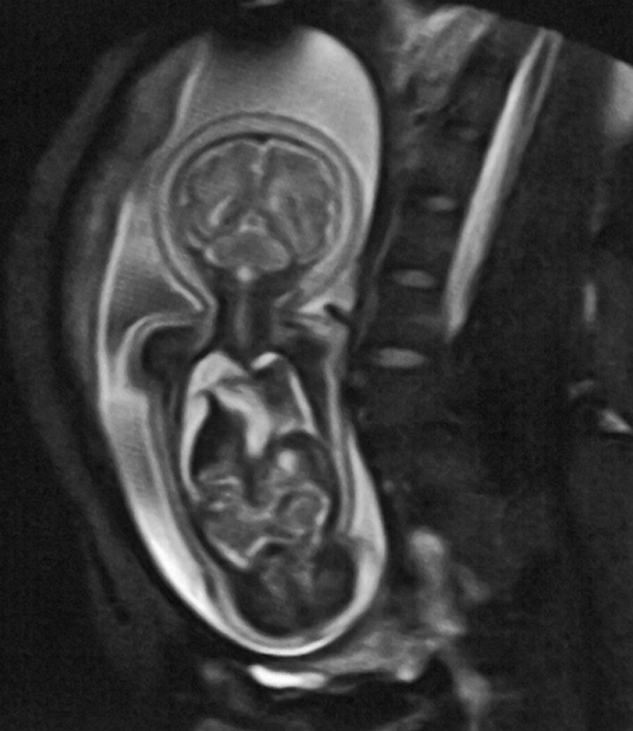

MR imaging is used for fetography (Figure 18-07), particularly for imaging the brain. At 3.0 Tesla (or higher magnetic fields), the specific ab­sorp­tion rate (SAR) and the increased noise may, at least potentially, adversely affect the fetus [⇒ Cannie 2016].

Figure 18-07:

MR fetography in the 32nd week of pregnancy.